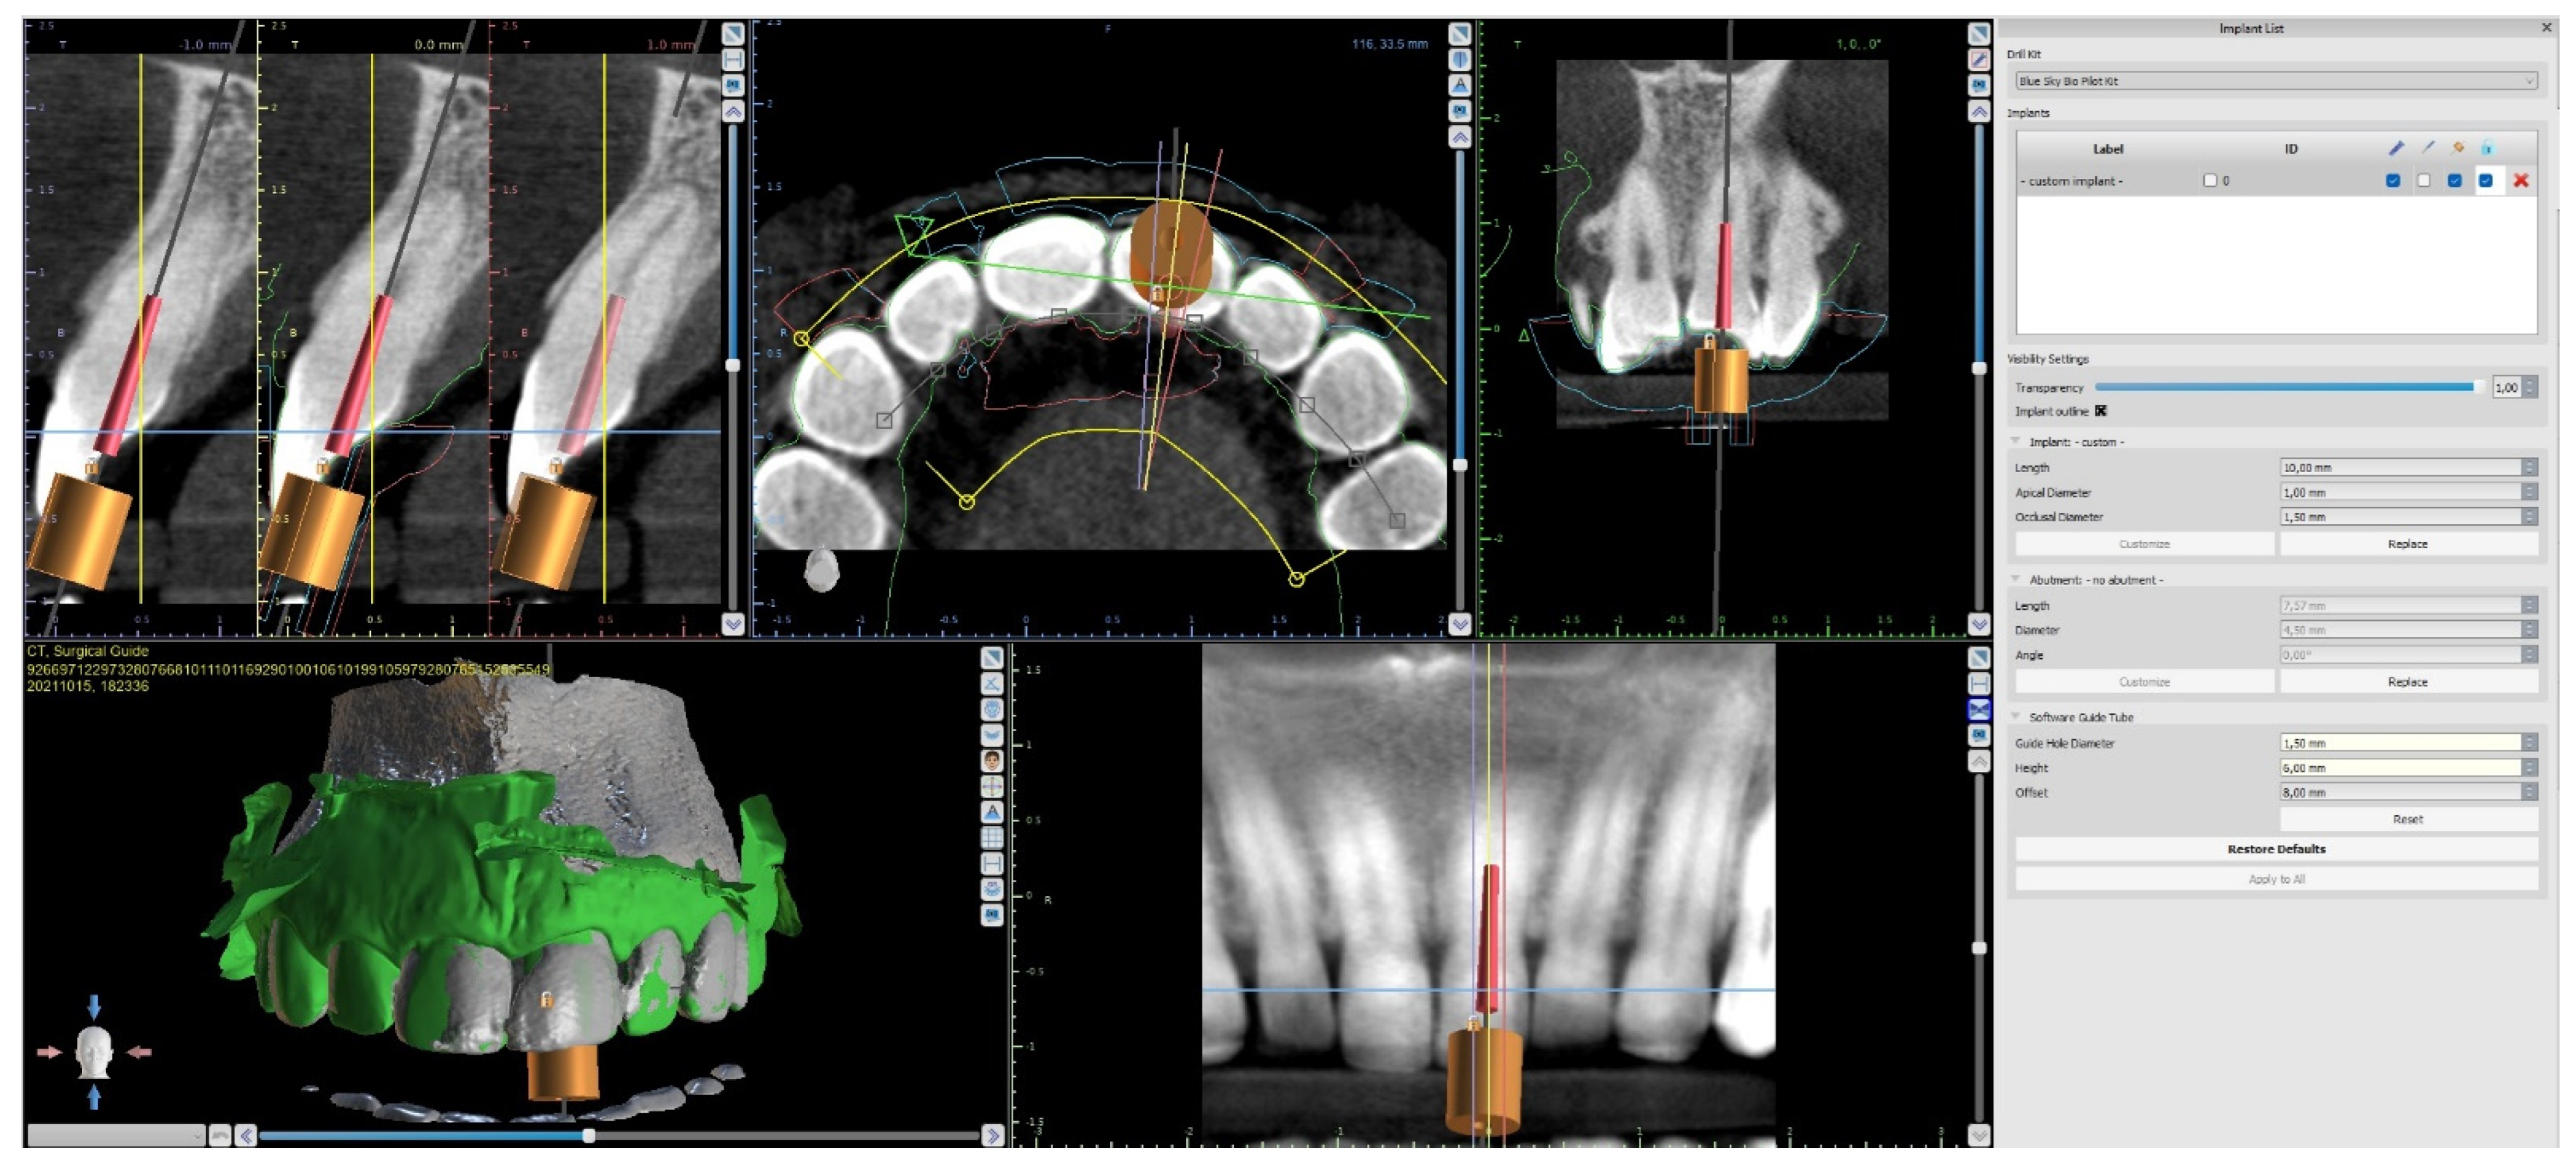

Three-Dimensional Treatment Plan

Three-Dimensional Treatment Plan and RCT

| Import DICOM and STL files into digital planning software |

| Design the virtual drill path and the endodontic guide |